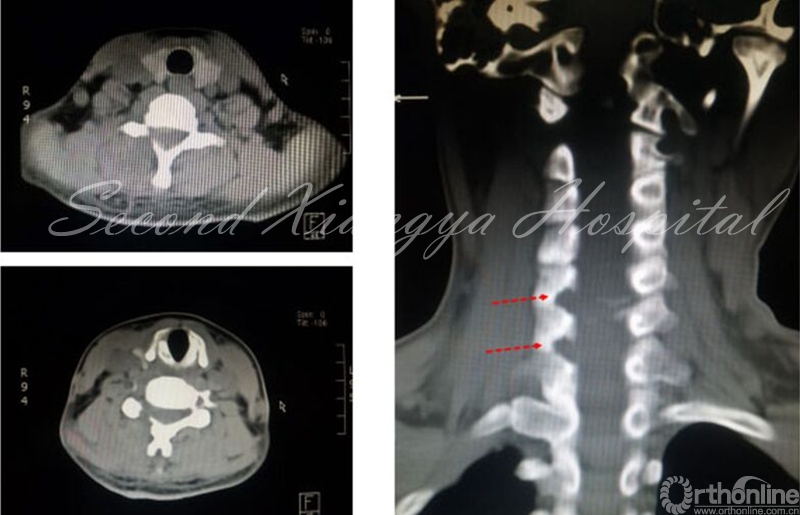

颈椎前路:与腰椎相比,颈椎由于毗邻结构复杂,穿刺风险相对较高,尤其在前路进行经皮内镜手术时更为明显。鉴于在颈椎开展经皮内镜脊髓神经损伤“零容忍”,穿刺时应特别注意技巧,即“气管投影,两指技术,皮触骨面,侧透避深。”术中透视时需找到气管侧方投影位置,然后用中指和无名指将血管鞘和内脏鞘推挤开,直至皮肤触及骨面,在两指之间穿刺入椎间隙后需透视证实未进入椎管,以确保脊髓安全。

经皮内窥镜在颈椎中的应用,有后路经椎间孔入路,前路经椎间隙和椎体两种入路。后路经椎间孔入路的适用范围主要包括C3-7神经根型颈椎病、颈椎间孔骨性狭窄,亦有部分颈椎管局限性狭窄患者可以采取后路内镜下椎管减压的手术方式。前路经椎间隙适合中央型髓核突出,经椎体用于髓核脱垂类型,不适合颈椎不稳、成角、钙化、间隙高度<4mm和严重压迫者。

颈椎前路:

与颈椎后路相比,前路由于入路复杂、毗邻结构重要和颈椎解剖限制,通过前路进行髓核摘除有较大争议。对于平间隙水平的突出,可以通过经椎间隙或椎间孔进行减压操作,对于移位到椎体后缘者,可以考虑经椎体进行,但操作难度较大。颈椎前路经皮内镜手术高的围手术期并发症,以及远期疗效问题,仍然需要我们对这一入路,通过循证医学角度,来科学看待,客观分析。